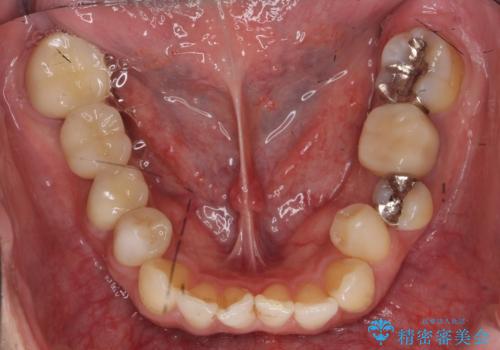

右下7については、遠心の歯の高さがなく、また、同様に歯肉縁下にカリエスがあったため、手術を行い改善しました。

- 右下567ブリッジ:43万円(ジルコニアクラウン10万円x3、仮歯1万円x3、APF10万円)、右下4:10万円(emaxクラウン7万円、仮歯1万円、ファイバーコア2万円)(税別)費用は治療当時の料金となります

手術はディスタルウェッジとAPFを併せて行なっています。